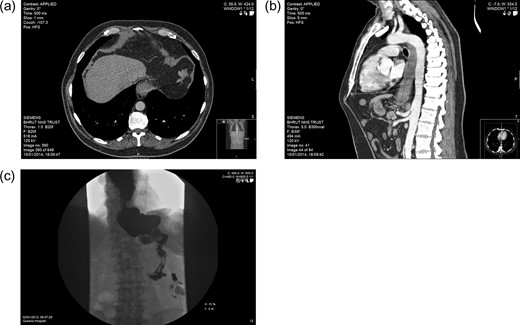

Imaging. PM: (a) axial CT section showing hypodensity in segment VIII of the liver, likely representing metastasis. BH: (b) Sagittal CT section demonstrating features of malginancy in the distal third of the oesophagus; dilatation of the middle and upper parts is notable owing to distal stenosis, and a soft tissue-density lesion is apparent in the final 5 cm. BH: (c) barium swallow study showing stasis in the distended lower oesophagus, with almost no contrast observed entering the stomach.

The following CT scan showed a 5 cm long thickening of the lower oesophagus extending to the gastro-oesophageal junction, with nodal involvement in segments 2 and 5 (Fig. 3b). Further hypodense metastatic lesions were identifiable in the liver. There was also evidence of peritoneal disease, in the left para-colic gutter and right supra-hepatic space. Tissue biopsies confirmed a poorly differentiated intestinal-type adenocarcinoma. It was subsequently arranged for BH to have a stenting procedure to relieve his dysphagia, and palliative chemotherapy.

Biopsies indicated a poorly differentiated adenocarcinoma (Fig. 2). CT scan suggested metastatic deposits in the liver and right kidney, alongside lymph node irregularities in coeliac axis and gastric lesser curve (Fig. 3a). A PET scan demonstrated localised regional uptake. The patient was commenced on palliative treatment, which included an endoscopic stent to the lower oesophagus and EOX chemotherapy. Prior to his diagnosis of cancer, PM only suffered from hypertension. His performance status at the time of commencing palliative chemotherapy was 1. Sadly he passed away shortly before he was due to commence cycle 2 of chemotherapy.